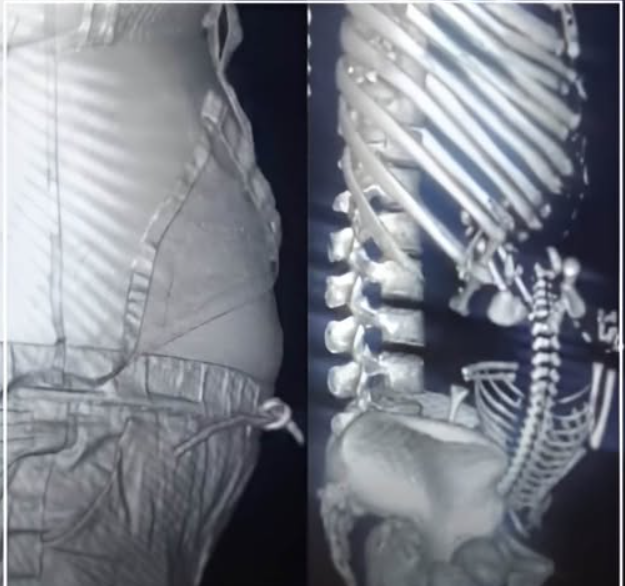

然而,當超音波與X光影像結果出來時,診間的空氣瞬間凝結。影像中清楚顯示,並非什麼腫瘤或發炎,而是一個已經完全發育成熟、甚至已經「入盆」準備迎接世界的胎兒骨骼影像。

兩小時的「奇蹟」與驚嚇

就在醫生還在思考如何與少女溝通這份影像結果時,少女的腹痛轉為規律的陣痛。兩小時後,在急診室的一陣忙亂中,一名健康的嬰兒啼哭落地。少女從「腹痛就醫」到「升格當媽」,過程快得讓全家人都反應不過來。